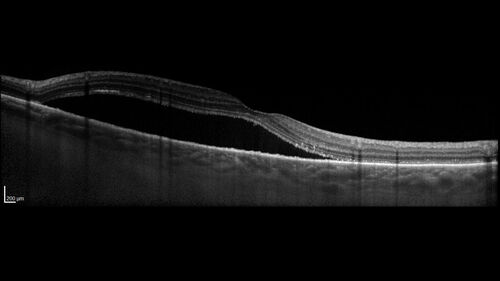

Serous Macular Detachment from Small Choroidal Melanoma

72 year old female misdiagnosed as CSR who had small choroidal melanoms.